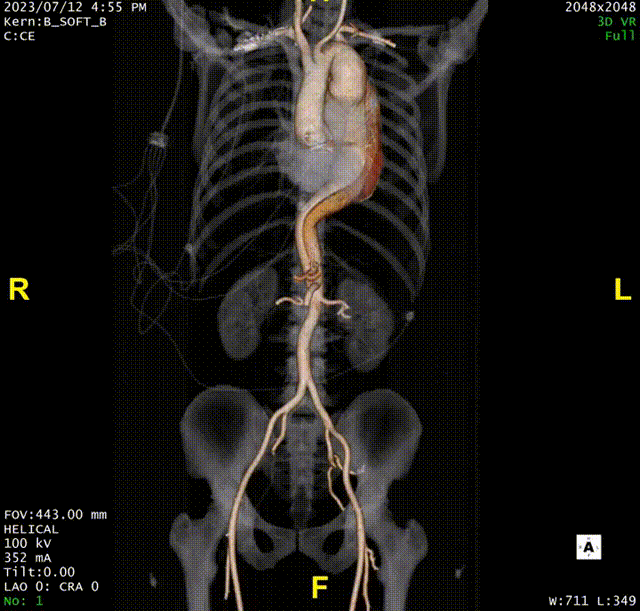

术前CTA评估与测量

术前CTA提示主动脉夹层(Stanford B型,Debake llI型),主动脉弓及降主动脉瘤样扩张,累及左锁骨下动脉起始段,管径最粗约7.4cm,夹层初破口位于降主动脉起始段,向下累及至腹主动脉(约平胸12椎体水平),真腔小,假腔大,腹腔干发自混合腔,肠系膜上动脉、下动脉,双肾动脉均起自真腔,双肾灌注未见差异。

术前三维重建